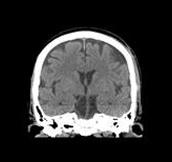

2.0 sec/rot, normal scanning, 0.625mm x 32i, 150mA. High image quality using normal scanning 64i mode for head MPR images